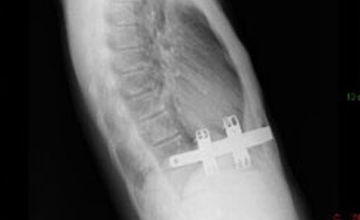

Pektus Arkuatum

Pektus Arkuatum (Mikst Deformite)

Pektus ekskavatum sternum ve kıkırdak kostaların değişik derecelerde depresyonu ile karakterize ...